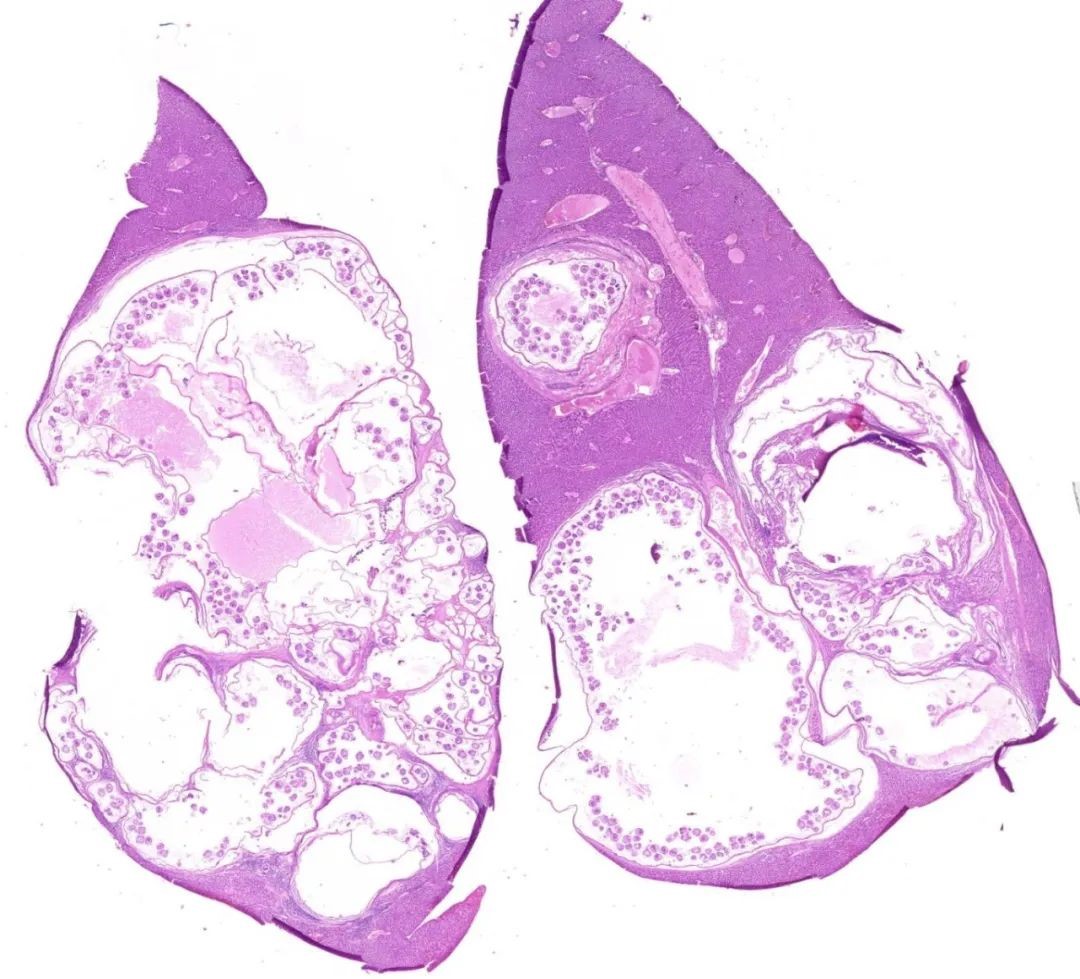

图3 泡型棘球蚴病的病理切片显微图像(取自于普通田鼠体内病灶),可见脏器内大量的棘球绦虫幼虫(原头节)